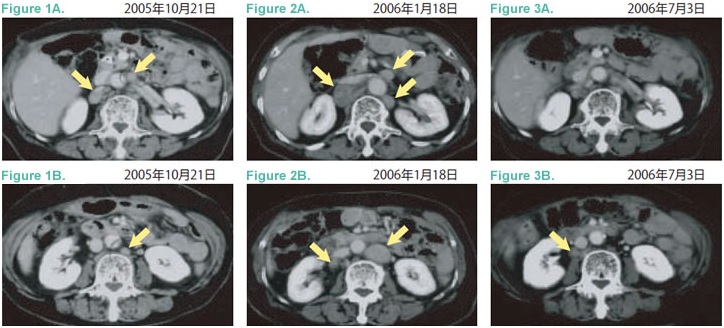

2005年10月腫瘤標(biāo)志物再上升,腹部CT顯示旁大動(dòng)脈淋巴結(jié)復(fù)發(fā)(Figure1A、B)。化療副作用腹瀉、強(qiáng)烈惡心,體重明顯先將,隨機(jī)中止TS-1,進(jìn)入維持性支持治療。2005年11月開(kāi)始服用中草藥。2006年1月18日發(fā)現(xiàn)新的淋巴結(jié)轉(zhuǎn)移,及原病灶增大(Figure2A、B),左鎖骨上淋巴結(jié)轉(zhuǎn)移。

2006年3月24日開(kāi)始詢(xún)問(wèn)免疫細(xì)胞治療,PS0,左鎖骨上淋巴結(jié)腫大可觸。4月7日開(kāi)始體淋巴活化治療(CD3-LAK),每2周1次。截至6月20日共治療6次。患者本人定期往福島縣溫泉療養(yǎng)。此間CA19-9指標(biāo)在下降,左鎖骨上淋巴結(jié)縮小,觸診已經(jīng)摸不到。7月3日CT影像顯示旁大動(dòng)脈淋巴結(jié)緩解(Figure3A、B)。之后該患者每6周接受一次免疫細(xì)胞治療,直至發(fā)稿,患者全身狀態(tài)良好,食欲佳。